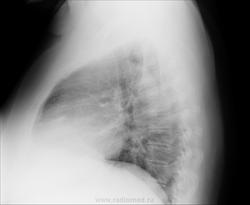

Женщина, 63года, жалобы на длительный кашель, общую слабость. Слева адгезивный плеврит? На боковом треугольная тень от корня? Помогите с диагнозом (рентгенолог будет только на следующей неделе).

Увеличение левого желудочка, усиление дуги аорты, диффузное усиление легочного рисунка. Картина может соответствовать явлениям застоя в малом круге кровообращения.

А почему бы тени не быть плевральными спайками? Тоже похоже,.. значит, близко плеврит.)